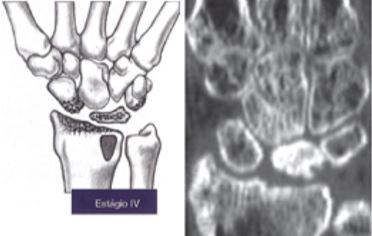

Como é o estágio IV de Lichtman

A

• Alterações artríticas na radiocarpal e mediocarpal

• fromação de osteófitos